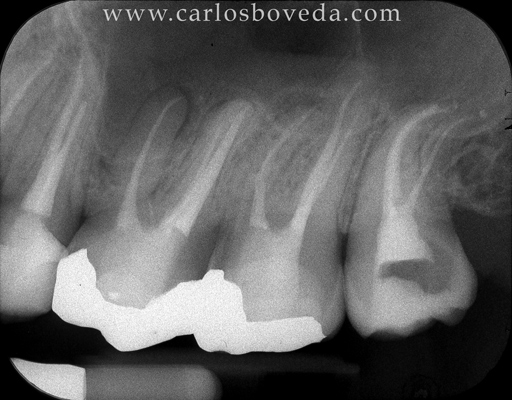

17